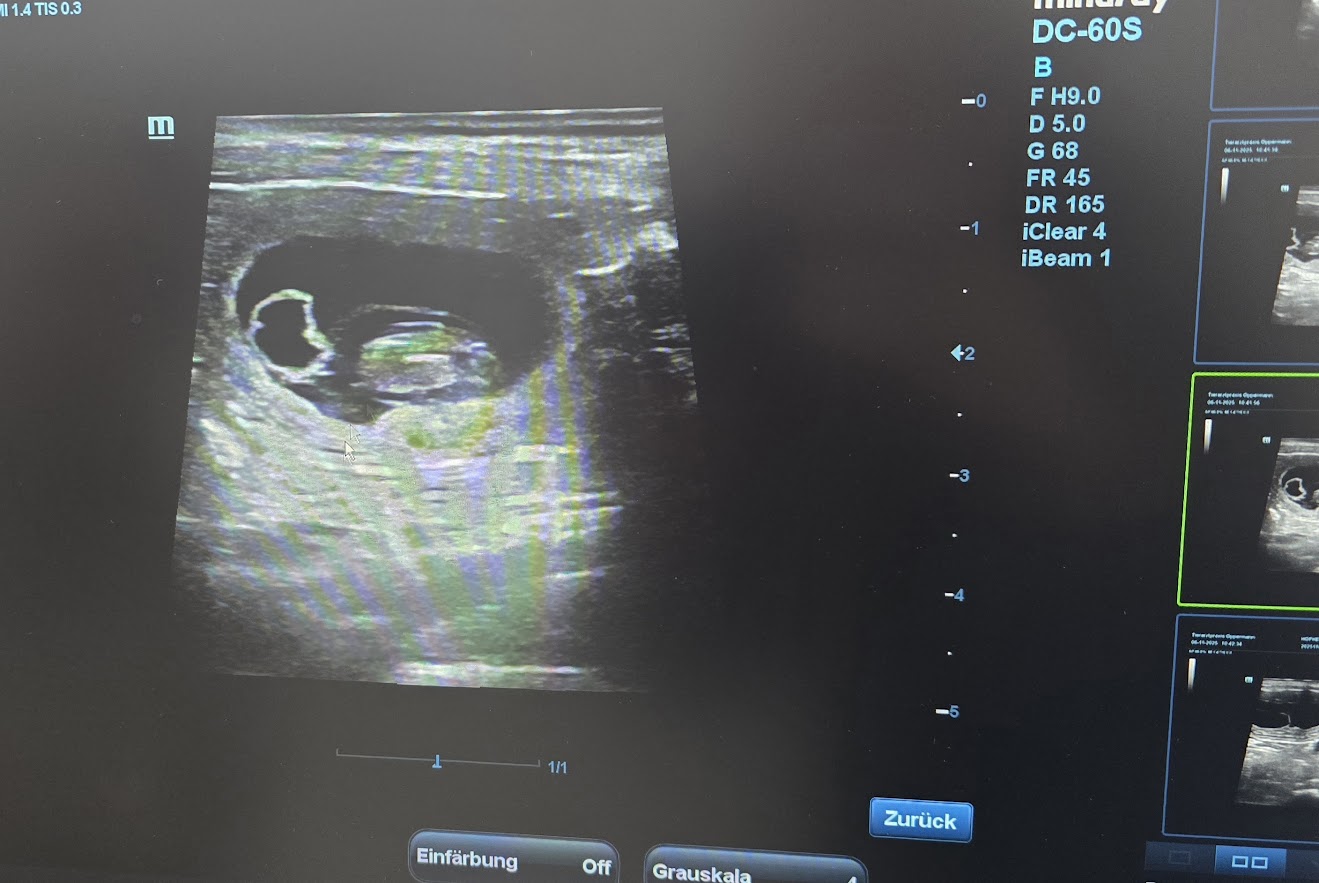

Ultraschalltermin

Voller Aufregung freuen wir uns auf den 06. November! Amiras Ultraschalltermin steht an.

Die Freude ist riesig und wir können mitteilen, dass es im Dezember bei uns Welpen gibt.